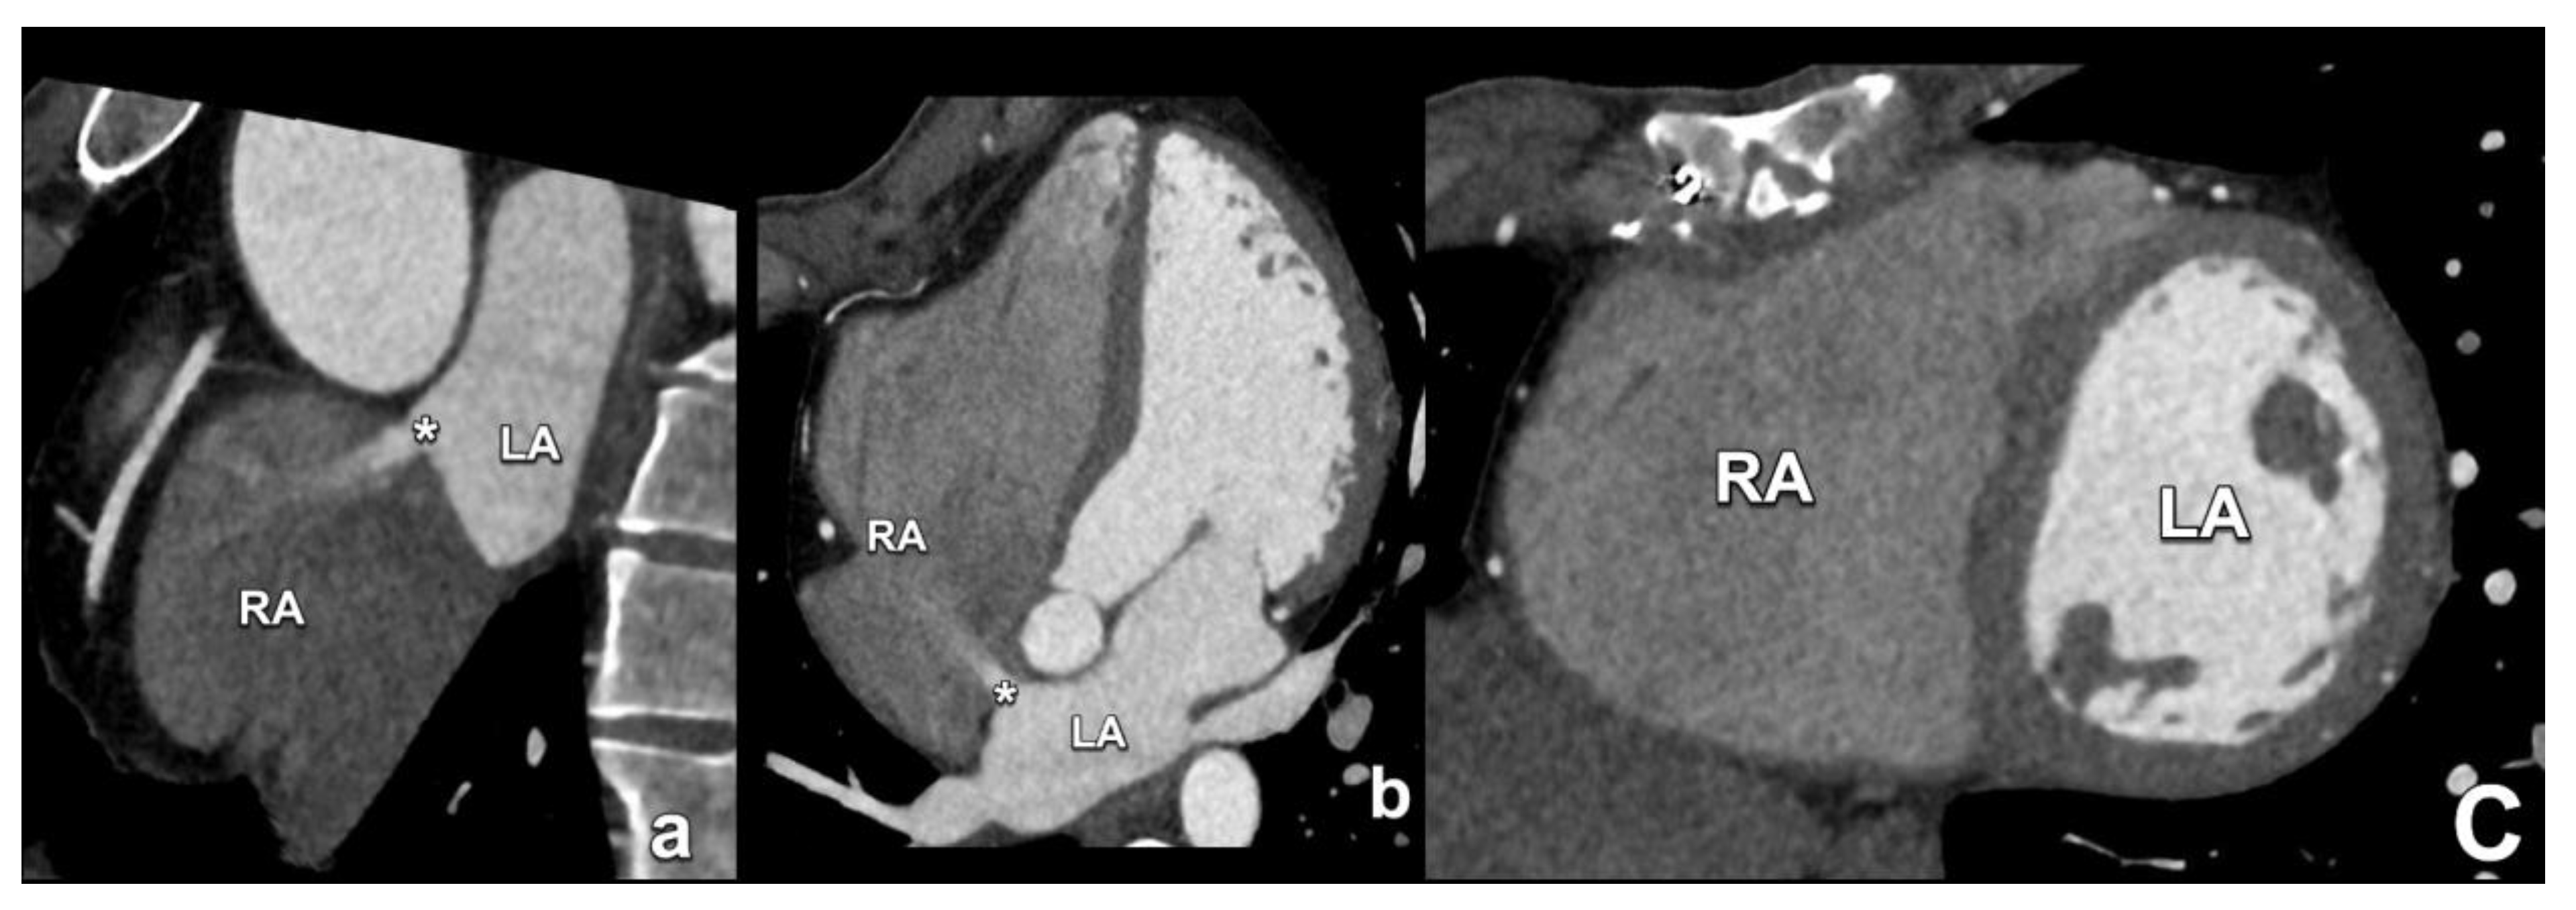

2. Atrial Septal Defects

- Yasunaga, D.; Hamon, M. MDCT of interatrial septum. Diagn. Interv. Imaging 2015, 96, 891–899. [Google Scholar] [CrossRef]